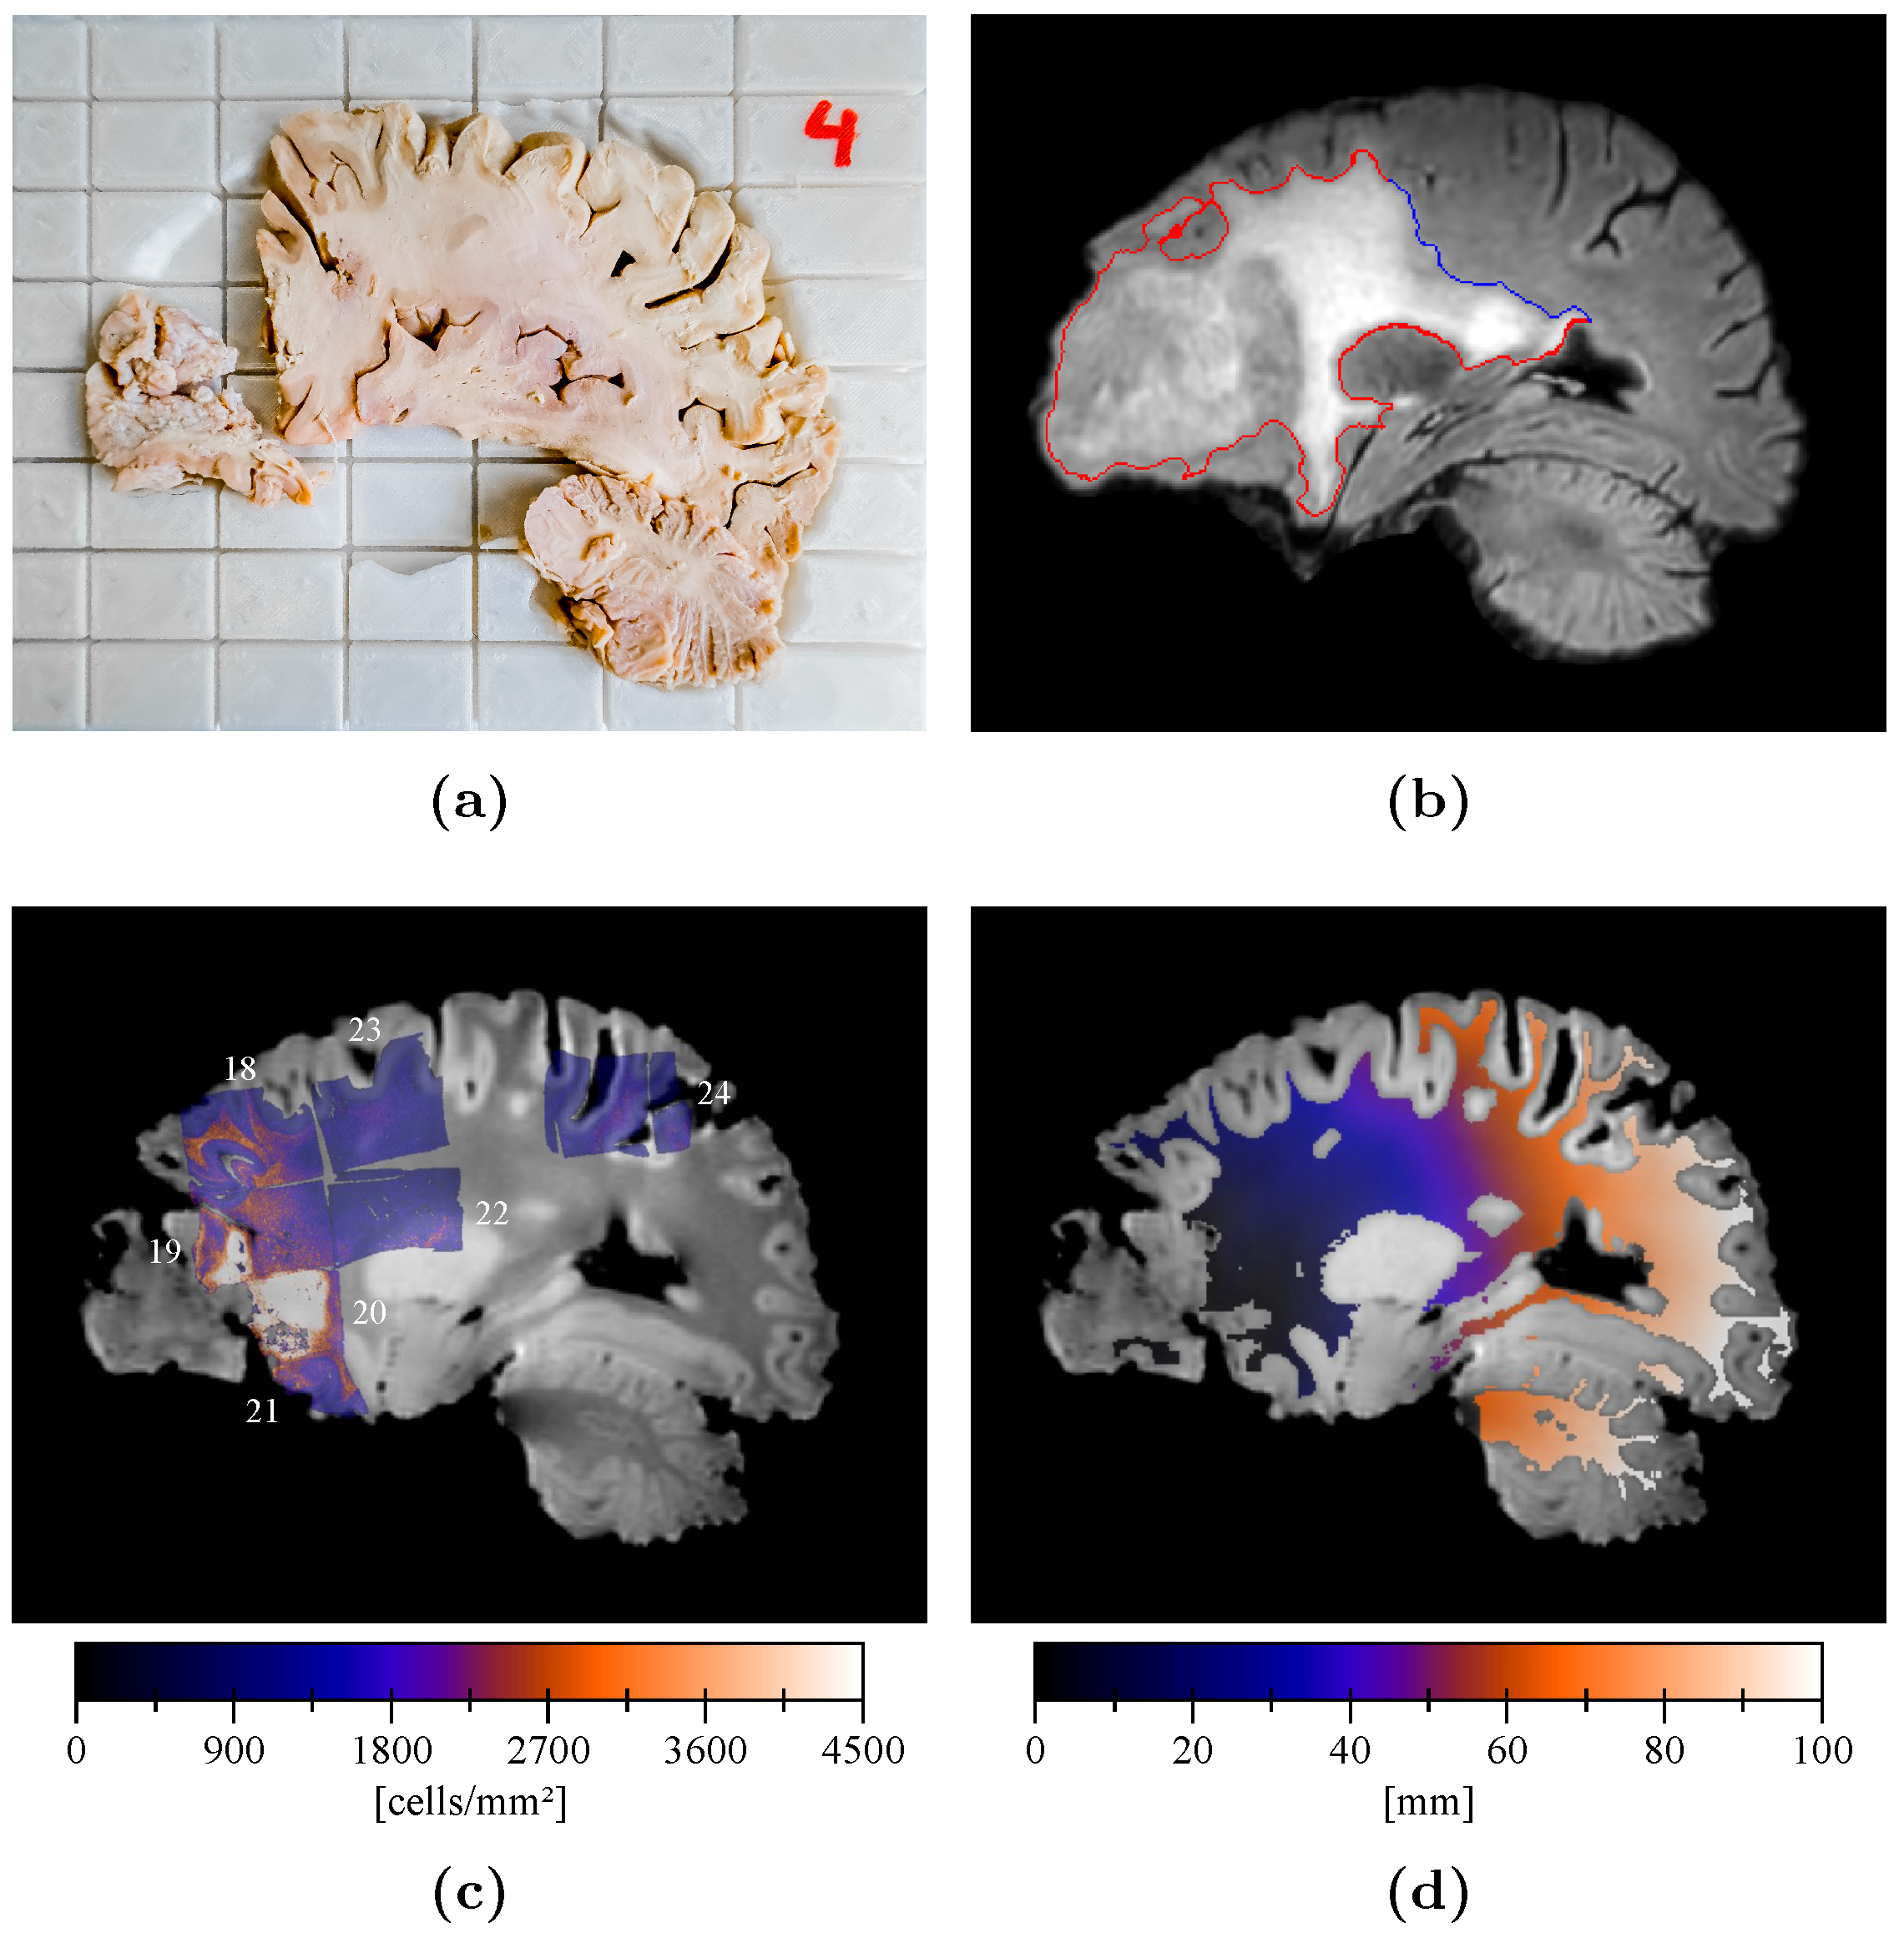

2.4. Sample Processing and Analysis

2.5. Cell Density Maps

2.6. Cell Density Maps to Ex Vivo T1 Registration

2.7. Edema Delineation

2.8. Distance Map

3. Results